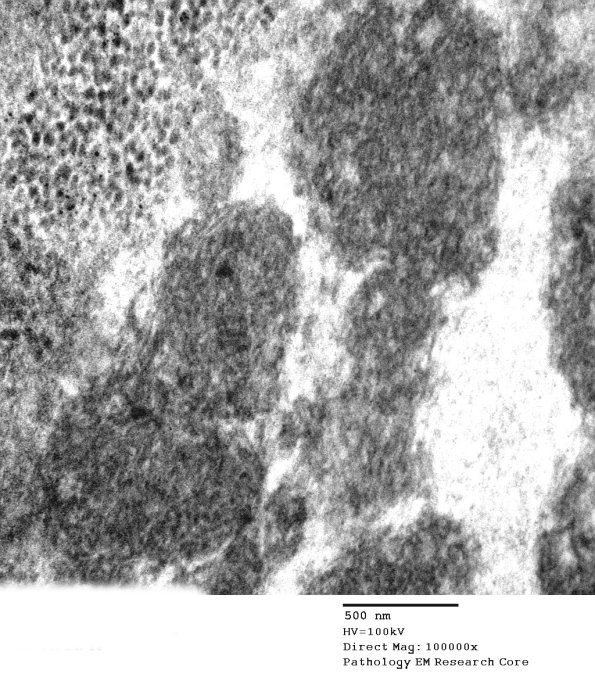

In the eccrine ducts there were scattered cytosomes which contain one or more inclusions characterized by vague tubulovesicular elements which are most compatible with curvilinear bodies of NCL, although they are not a precise match. (electron micrograph)